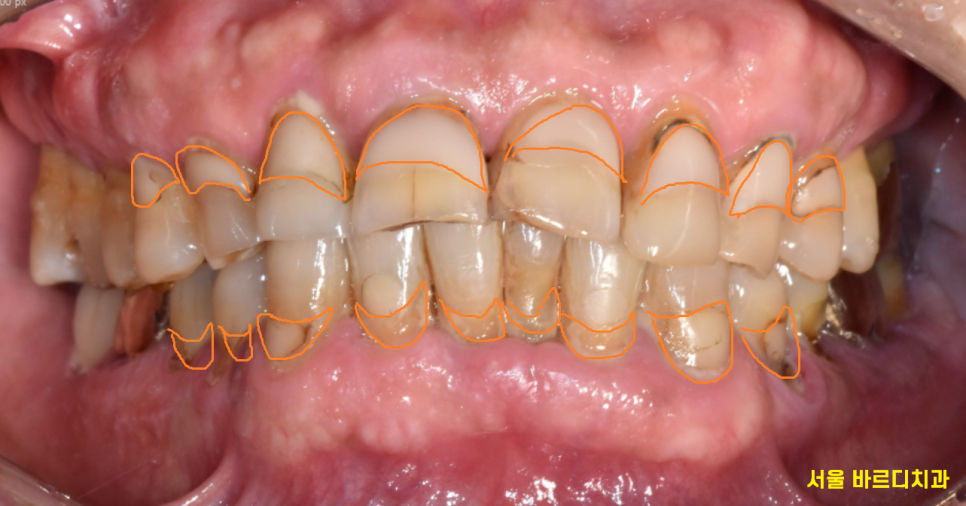

잇몸 주저앉음의 대표 증상은

치아가 길어보입니다.

잇몸이 내려가 치아 뿌리가 들어나기 때문이죠

▼사진▼

환자분은 오랜 시간 잇몸 주저앉음으로

치아 전반적으로 다 떼워진 상태입니다.

잇몸이 내려가서 치아가 흔들거렸지만

계속해서 잇몸치료 받으며 관리 받으셨는데요.